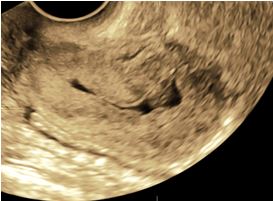

Immagini in 3d di adenocarcinoma endometriale in cui si denota un’infiltrazione del miometrio superiore al 50% dello spessore miometriale e assenza di coinvolgimento dello stroma del canale cervicale.